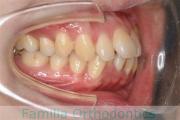

No.22V-029

- 叢生

- 上顎前突

- 19歳

- 男性

- 8448

- FEA 022

- 92万円

でこぼこを治したいということで来院されました。上下左右から親知らずも第一小臼歯も抜歯が必要で、歯科矯正アンカースクリューを併用して大臼歯を後ろに引っ張りながらの治療でした。3年弱、35回程度の通院が必要でした。

叢生が著しく、後戻りのリスクがあります。またアンカースクリューが必須のため、もしもスクリューが安定しないと、治療が難しく長くなってしまう恐れがありましたが、幸い脱落は見られませんでした。